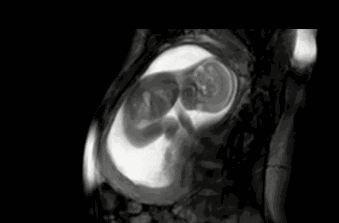

怀孕28周了 , 最近胎动得厉害 , 一般是很正常的现象 , 其实宝宝的胎动大概在怀孕7、8个月左右会达到高峰 。

怀孕28周了 , 最近胎动得厉害 , 是怎么回事

怀孕28周也就是7个月左右 , 此时胎动得厉害主要是因为以下几点 。

胎儿大小适中:通常刚开始感觉到胎动时 , 宝宝还很小 , 因此胎动不会太厉害 , 而怀孕28周 , 胎儿大小适中 , 所以胎动会更为剧烈一些 。

子宫内空间较大:其实宝宝的胎动一般会经历由少到多 , 由轻微到剧烈再到减少这么一个过程 , 这其中的变化与胎儿的发育有关 , 也与子宫内的空间有关 , 当胎儿大小适中 , 子宫内空间又较大时 , 准妈妈就会感觉到比较厉害的胎动 。